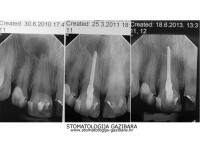

LIJEVO: 1a početno stanje,prednji zubi - DESNO: 1b nakon završetka terapijee LIJEVO: 2a revizija punjenja korijenskih kanala,višekorijenski zubi        <br />

DESNO: 2b nakon završetka terapije LIJEVO: 3a  prije revizije punjenja,jednokorijenski zub<br />

DESNO: 3b  nakon završetka terapije LIJEVO: 4a liječenje granuloma ,početno stanje<br />

SREDINA: 4b stanje nakon 9 mjeseci<br />

DESNO: 4c stanje nakon 3 godine, granuloma više nema !